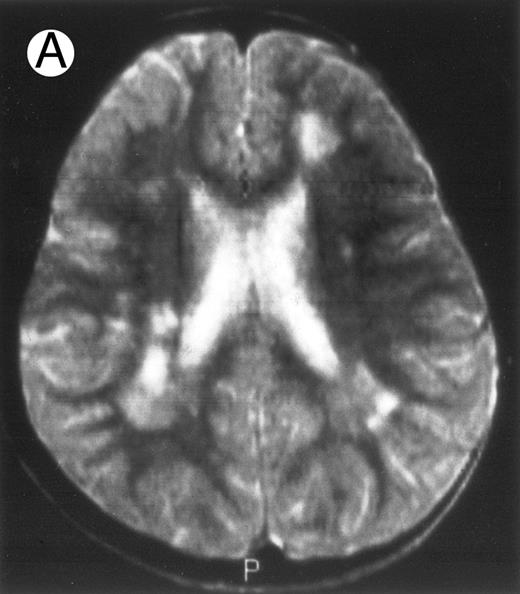

Evolution of brain lesions during HLH. (A) MRI of a 41/2-year-old girl showing focal white matter hypersignal on T2-weighted images. (B) MRI of the same child 1 year later with an important atrophy of both the white matter and the cortices.

Together, 19 patients had primary severe CNS disease progression or CNS relapse (Fig 1). Three of 19 had a CNS relapse characterized by meningitis only. Neurological symptoms occurred in 16 of these 19 patients (9 from the onset and 7 after the initial meningitis) (Fig 1). No clinical or neuroradiological difference was detected between the patients who developed neurological symptoms as the initial CNS manifestation or after initial meningitis (Table 1). The occurrence of these neurological manifestations marked a turning point in the evolution of the disease, as chemotherapy led to an improvement of the neurological symptoms in only three patients despite the use of intensive treatment by MTX IT. In these three patients, neurological sequelae persisted after the first symptoms and a relapse occurred within 3 to 10 months. Brain imaging was repeated during chemotherapy for four patients with progression of the CNS disease: in three patients, a severe brain atrophy developed (Fig 3A and B) and in the last patient who initially had contrast enhancement in cerebellar white matter, a cerebellum parenchymal loss was observed (Fig 2C). All of these 19 patients treated by chemotherapy only (n = 15) died during a last episode of coma and brain stem symptoms associated with a systemic hemophagocytic syndrome, 6 ± 6 months after the first neurological symptom (irrespective of the age at this first event). Four of these 19 patients were transplanted (one patient received an HLA-identical BMT, three an HLA-partially identical BMT). Median delay between diagnosis and BMT was 14 months (range, 2 to 20 months). All of these four patients died of BMT-related toxicity and/or disease progression.

Abnormalities on brain imaging appeared to roughly parallel the severity of clinical manifestations. All patients with neurological symptoms, but also half of the patients with initial meningitis, had abnormal brain imaging usually consisting of a combination of diffuse white matter abnormalities and necrotic areas with parenchymal volume loss, as previously described.8,23 In patients with isolated meningitis, however, only white matter abnormalities were detected, whereas necrotic lesions and cerebral atrophy were found in patients with neurological symptoms. These lesions progressed despite chemotherapy. Previous neuropathological studies have demonstrated infiltration by monocytes and activated lymphocytes of leptomeninges and brain parenchyma along penetrating vessels.24,25 Infiltration is associated with focal and confluent areas of myelin pallor, as well as neuronal loss, tissue necrosis, and cavitation,24,25 findings that were also demonstrated in the neuropathologic study of five patients in our series. Leukocytes infiltrating the CNS probably secrete cytokines and other neurotoxic factors, such as tumor necrosis factor-α (TNF-α), which may be responsible for the myelinic alteration observed in neurologically asymptomatic patients. Infiltrating leukocytes could also activate in parallel the numerous resident brain macrophages (the microglial cells) and astrocytes, which in turn, can secrete neurotoxic glutamate and free radicals.26